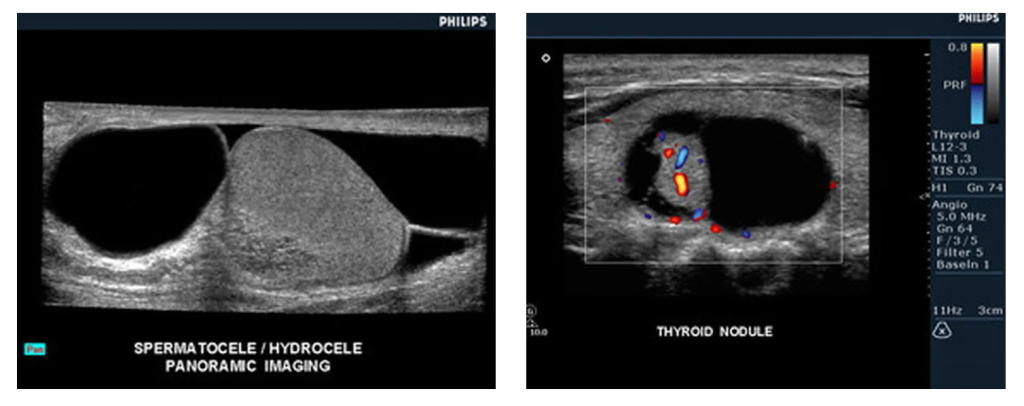

Клинические изображения Основные характеристики системы